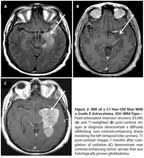

FIGURE 2

MRI of a 51-Year-Old Man With a Grade II Astrocytoma,

IDH

–Wild-Type

A 51-year-old man presented with complex partial seizures, and MRI demonstrated a nonenhancing, infiltrating lesion involving the anterior and medial left temporal lobe, insula, and thalamus (Figures 2A and 2B). A biopsy was performed, and pathology was interpreted as grade II infiltrating astrocytoma. The patient was treated adjuvantly with involved-field radiation; however, 10 months after diagnosis, an MRI revealed new enhancement throughout the left temporal lobe causing significant mass effect (Figure 2C). Subtotal resection and biopsy demonstrated transformation to GBM. Retrospective analysis revealed this tumor to be IDH1−wild-type. He was treated with repeat radiation (2880 cGy) and concomitant temozolomide; however, he died a few months later. Overall survival from diagnosis of grade II astrocytoma was 15 months.